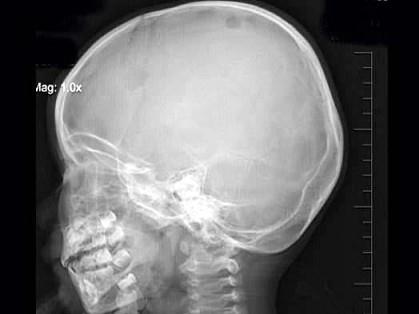

问题 3岁,男,发热伴头顶部局限性疼痛1周,右额顶部可见局限性骨缺损,最可能的诊断是?(?)

选项 A.蛛网膜颗粒压迹 B.先天性颅骨缺损 C.嗜酸性肉芽肿 D.局限性骨皮质缺损 E.以上均不是

答案 C